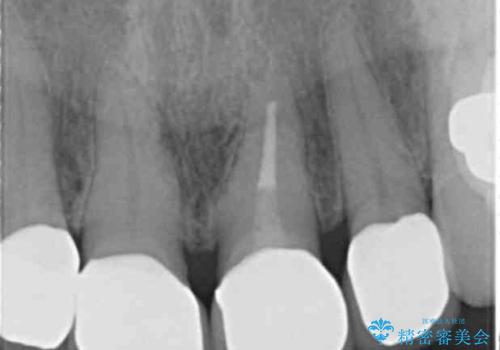

- 前歯のセラミック治療から5年経過した患者様です。

数年ぶりにメンテナンスに来て下さいました。

治療した上の前歯4本は全く問題がないそうで、「どうしてこんなに長持ちするんですか?」と聞かれた程です。

5年前のクラウン装着時と比較したところ、歯肉が成熟し歯間乳頭ができており、より天然歯のように自然に見えました。

患者様の良好なセルフケアと精密な適合の良いクラウンにより、歯肉の腫脹や退縮も認められませんでした。

5年前に行った治療に大変ご満足頂き、他の部位も治療やホワイトニングを希望して下さいました。

クラウンの種類:ジルコニアオールセラミッククラウン スタンダード